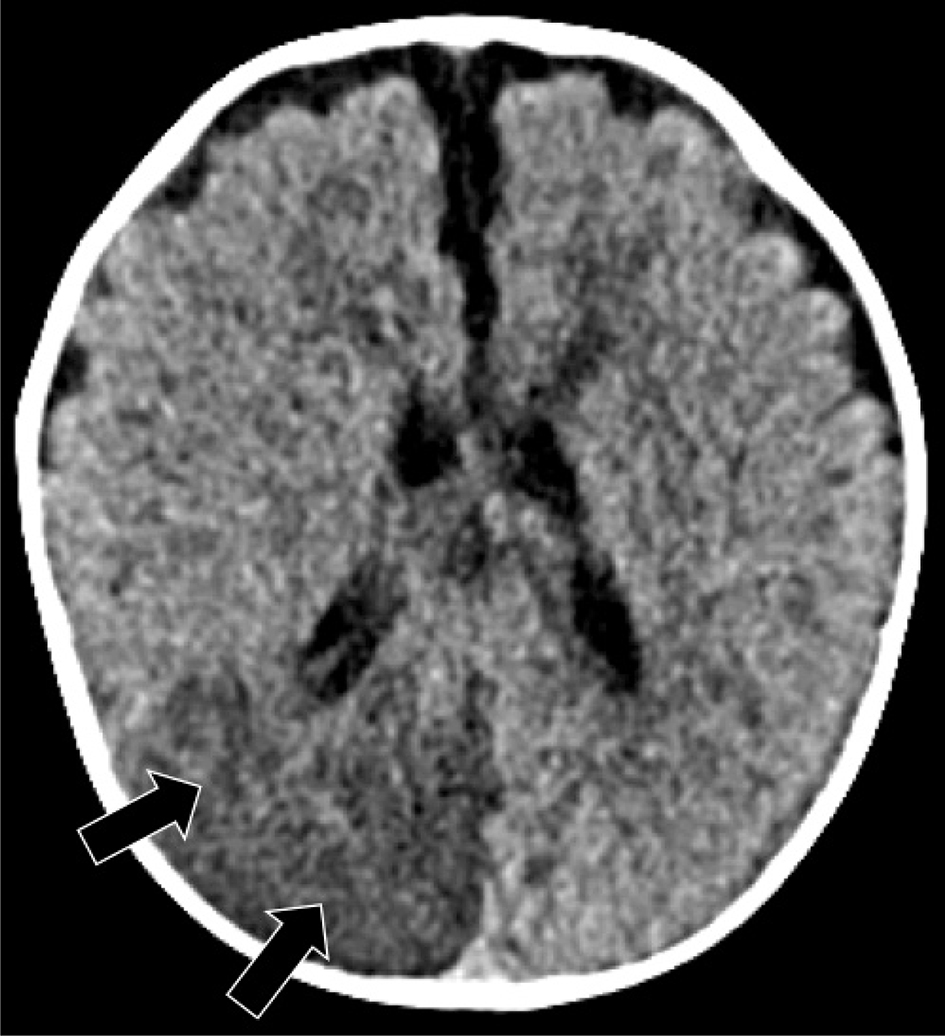

Periventricular venous infarction occurs in preterm infants as a consequence of germinal matrix hemorrhage, typically prior to 32 weeks of gestation (11). Germinal matrix hemorrhage may secondarily cause compression of the medullary veins, resulting in focal venous infarction in the periventricular white matter (100). Primary thrombosis of deep medullary vein can also be seen in full term neonates with congenital heart disease or with dehydration/metabolic acidosis, in the absence of germinal matrix hemorrhage, hypothesized to be related to hypoperfusion or impaired cerebral blood flow, and resulting in periventricular white matter venous infarct, often hemorrhagic (101103). The “iris sign,” a fan-shaped appearance of restricted diffusion or hemorrhage, most prominent in the deep frontal white matter, is a pathognomonic imaging sign of medullary vein thrombosis (Figure 10) (104). Delayed findings of periventricular venous infarction include periventricular white matter volume loss sparing the cortex and basal ganglia, focal irregularity of the ventricular margin, and hemosiderin staining (105). If spontaneous venous thrombosis is identified, the patient should be evaluated for disorders of coagulation (30, 97, 106113).

Fig 10

Figure 10. Medullary vein thrombosis and periventricular venous infarctions. Ex-premature at 32 weeks of gestation neonate, axial T2-weighted image (A) shows intraventricular hemorrhage (Black arrowhead), medullary veins thrombosis, and periventricular venous infarctions (arrows). A 7-day-old full-term neonate with severe dehydration. Sagittal T1-weighted (B) and axial GRE (C) images shows acute thrombus in the straight sinus (black arrow) and torcular and extensive thrombosis of the deep periventricular medullary veins (white arrowheads). Case courtesy of Dr. Tamara Feygin, Department of Radiology, Children’s Hospital of Philadelphia.